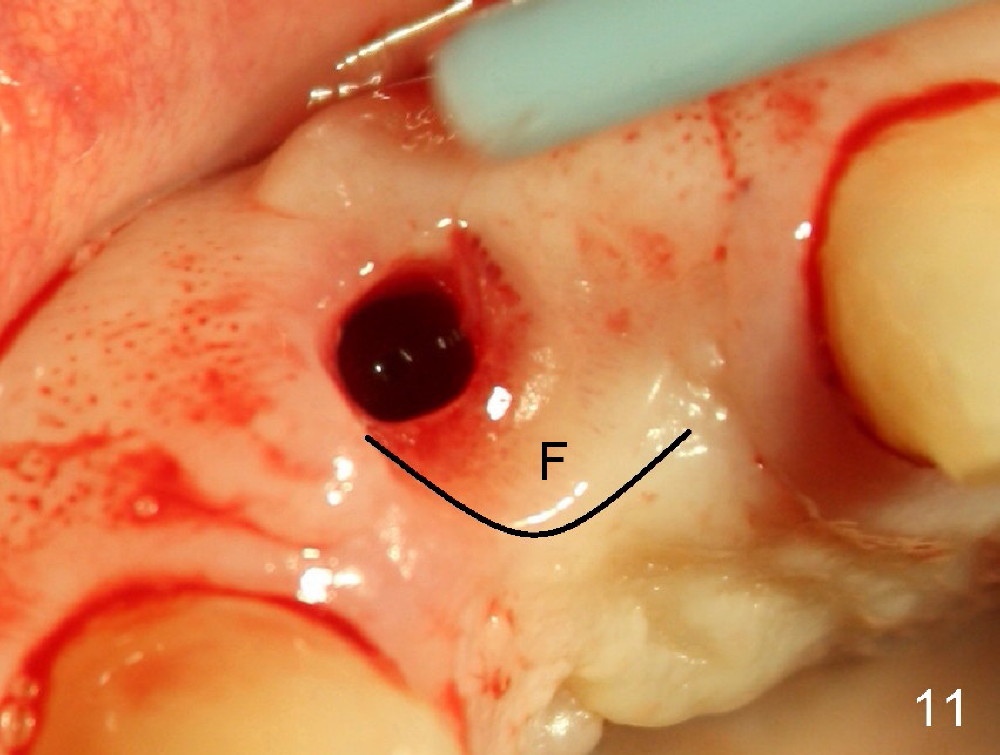

Malpositioned implant in the anterior region is cosmetically unacceptable. Immediate provisional allows us to note the issue immediately. The crown looks too long. Secondly, the provisional is easily dislodged, since the buccal aspect of the angled abutment is over trimmed (Fig.1). The implant (3.8x14 mm), which has been placed 3.5 months, is unexpectedly easily removed by reverse torque (Fig.2). The buccal wall is intact, whereas there seems to be enough bone lingually to place an implant. A small incision is made (Fig.11) so that the gingival tissue can be transferred buccally (Fig.12) and the immediate implant is to be placed palatally (Fig.13 white circle). There is no difficulty forming osteotomy in the palatal wall, followed by inserting 4.5x20 mm tap at the depth of 17 mm (Fig.3,5). But the tap is not palatal enough (Fig.4). By removing more palatal bone, the 4.5x17 implant (Fig.6) appears to be placed palatally enough for restoration (Fig.7; A: abutment; *: buccal gap). The biggest problem is that the palatal flap (Fig.7 arrowheads) cannot be pushed buccally; instead remains palatally. This leads to buccal tissue deficiency (Fig.8). Connective tissue graft is offered, but declined. The patient insists that she has low smile line. Following immediate provisional, mixture of allograft and synthetic graft is placed in the buccal gap (Fig.9). The overbuilt graft is held in place by perio dressing.